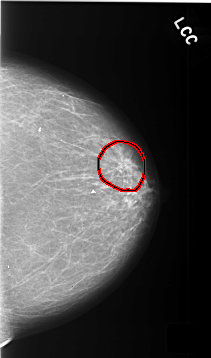

C_0340_1.LEFT_CC

FILE: C_0340_1.LEFT_CC.OVERLAY

TOTAL_ABNORMALITIES 1

ABNORMALITY 1

LESION_TYPE MASS SHAPE ARCHITECTURAL_DISTORTION MARGINS SPICULATED

ASSESSMENT 4

SUBTLETY 5

PATHOLOGY BENIGN_WITHOUT_CALLBACK

TOTAL_OUTLINES 1

BOUNDARY